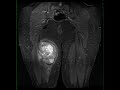

Synovial Sarcoma, Thigh

45-year-old male with a proximal posteromedial right thigh mass. There is a heterogeneous solid and cystic T1 hyper- and isointense lesion arising in the proximal right thigh semitendinosis muscle. The lesion is STIR hyperintense with partially circumscribed margins. There is heterogeneous enhancement with a peripheral rind of viable tumor posteriorly. At resection, the lesion was found to be a synovial sarcoma. Synovial sarcomas are intermediate to high-grade malignant soft tissue tumors often with an indolent course. Typical presentation is in adolescents and young adults with a slight male to female predominance. Clinical features include a slowly enlarging soft tissue mass. The most common location for synovial sarcoma is within soft tissues adjacent to large joints such as the knee. Treatment is with a combination of surgery and adjuvant chemoradiation therapy.